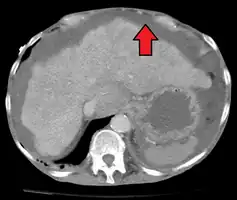

Liver cirrhosis with ascites

Ultrasound investigation is often performed prior to attempts to remove fluid from the abdomen. This may reveal the size and shape of the abdominal organs, and Doppler studies may show the direction of flow in the portal vein, as well as detecting Budd-Chiari syndrome (thrombosis of the hepatic vein) and portal vein thrombosis. Additionally, the sonographer can make an estimation of the amount of ascitic fluid, and difficult-to-drain ascites may be drained under ultrasound guidance. An abdominal CT scan is a more accurate alternate to reveal abdominal organ structure and morphology.